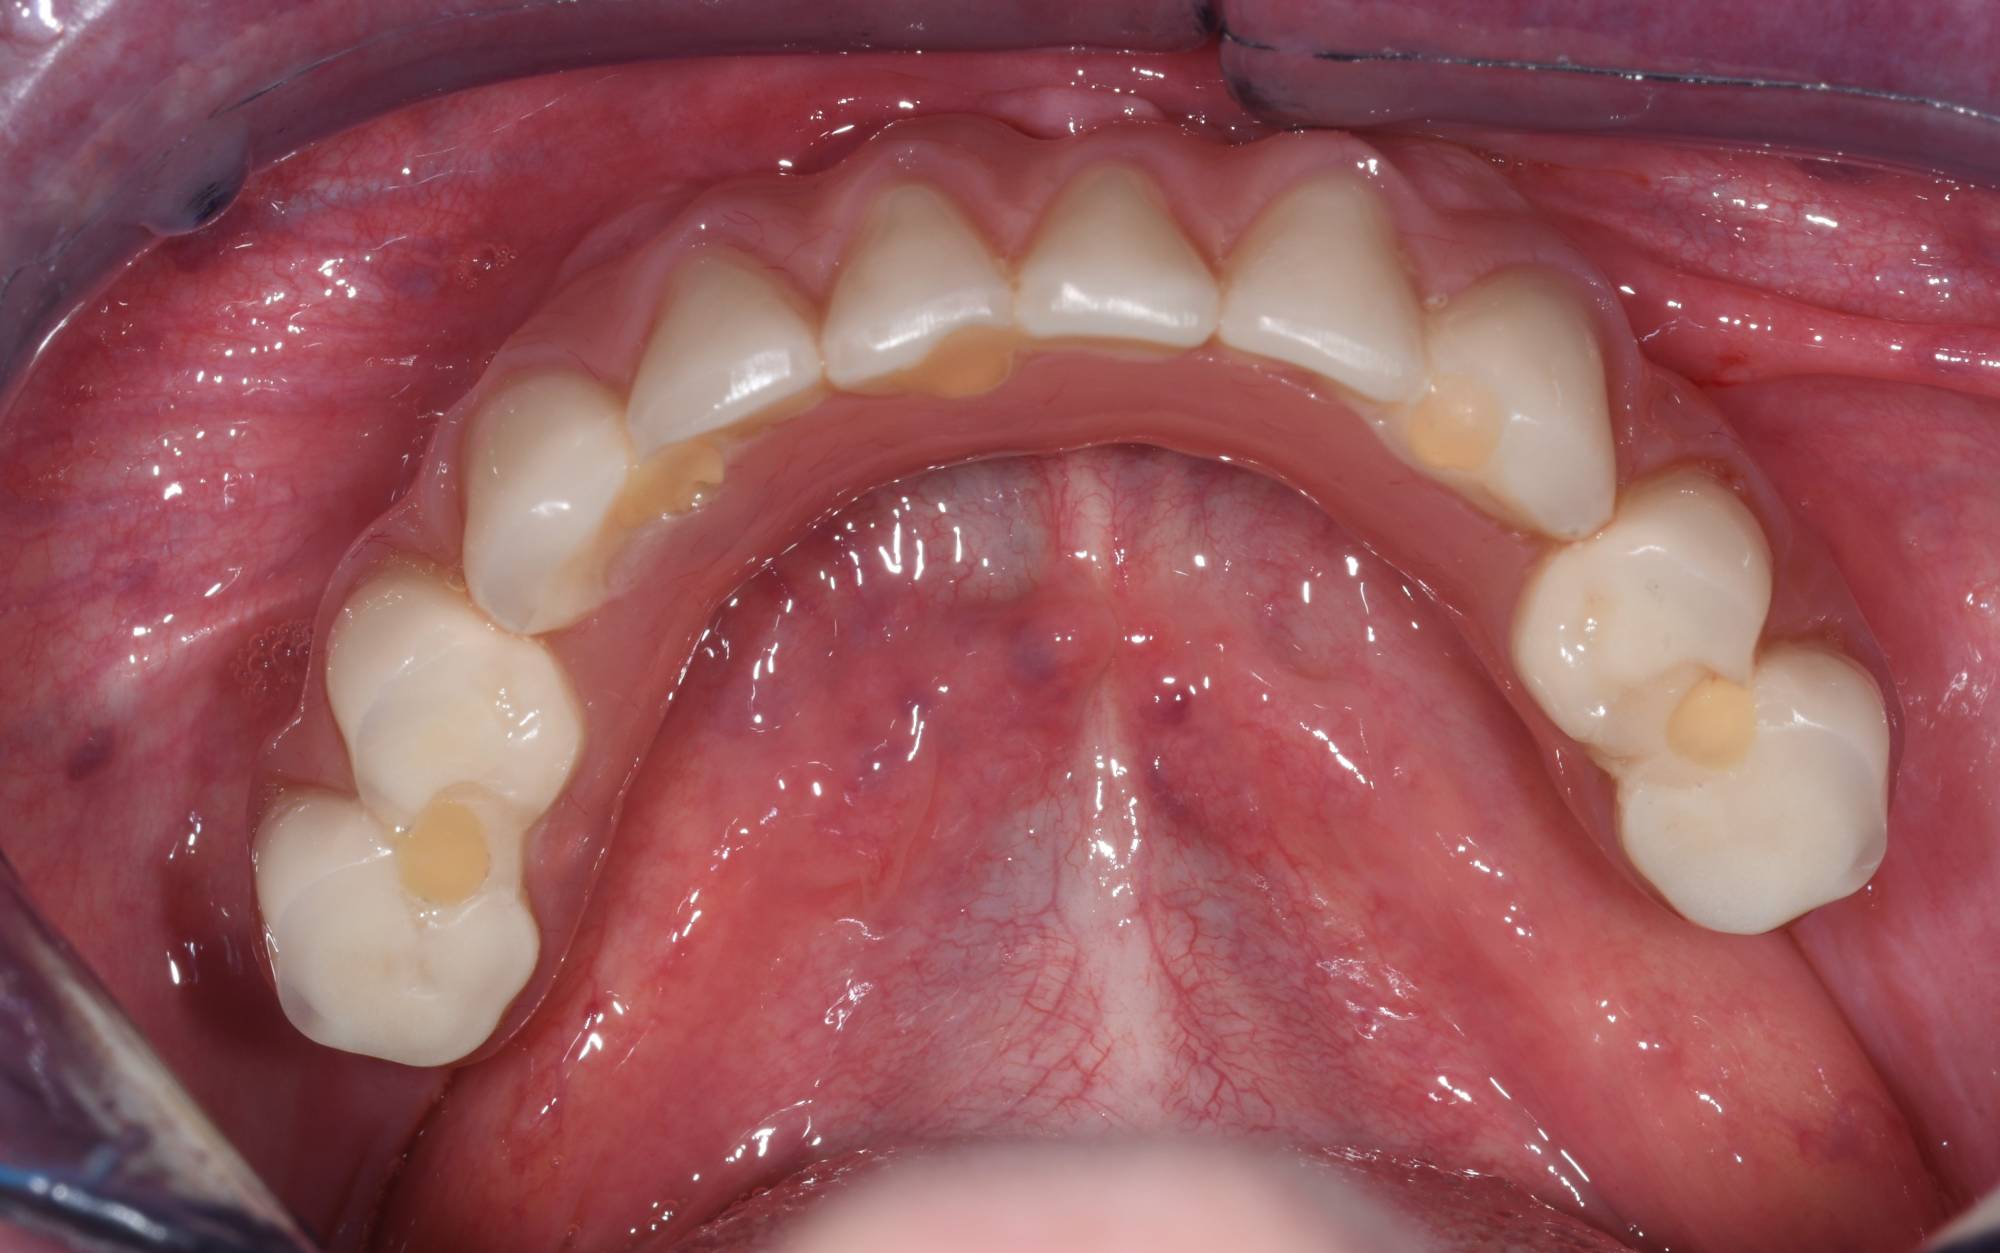

Come vedi dalle foto qui sotto, la paziente aveva perso numerosi denti e quelli rimanenti erano “traballanti”, pertanto non poteva più sorridere e mangiare normalmente. Per cui ho inserito gli impianti osteointegrati necessari per rimpiazzare tutta l’arcata inferiore. Nel giro di 2 giorni ha ritrovato sorriso e funzione con una protesi fissa provvisoria saldamente avvitata agli impianti.